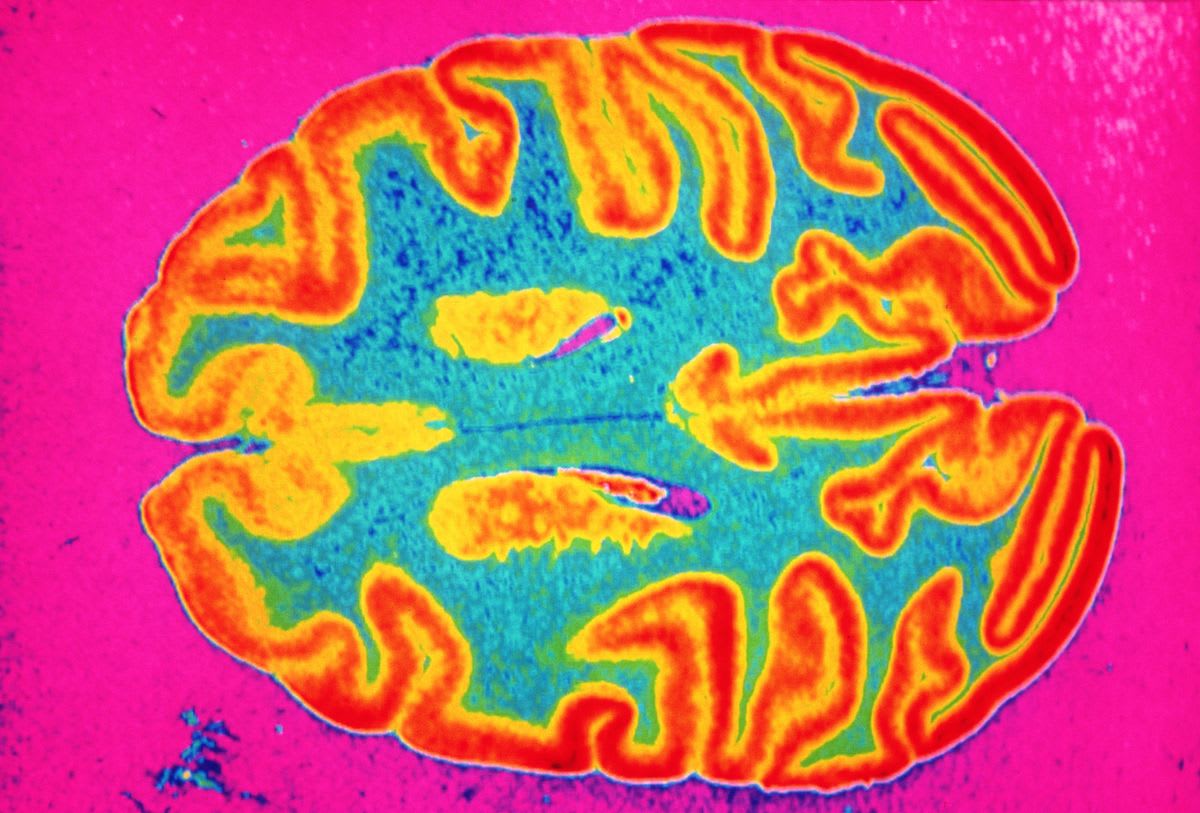

The findings aren't limited to lab animals. Oxford University researchers analyzed brain scans from 40,000 people and ranked alcohol among the top threats to cognitive health. Professor Gwenaëlle Douaud noted that alcohol specifically damages the brain regions most vulnerable to aging and dementia.